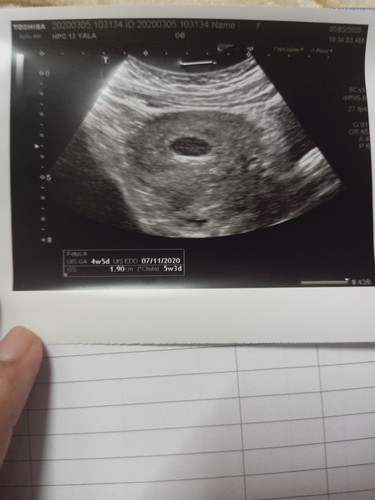

ทำไงดีค่ะอายุครรภ์9สัปดาห์แต่u/sแค่4สัปดาร์6วันค่ะช่วยแนะนำหน่อยค่ะ